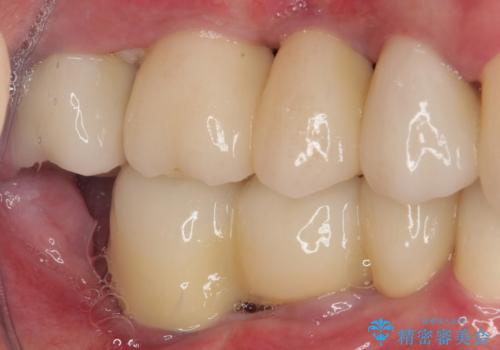

強い咬合力で奥歯がボロボロに インプラント治療による咬合回復と全顎セラミック治療

欠損部はインプラントによる補綴治療を行うこととし、臼歯部が安定した後に、上下前歯部をオールセラミッククラウンにて補綴治療を行うこととしました。

上顎前歯に歯周ポケットの深い部分がありましたが、インプラントの仮歯で奥歯がしっかりと噛めるようになると、1年程度で深い歯周ポケットは解消されました。

前歯部の審美面も大幅に改善され、大変満足していただけました。